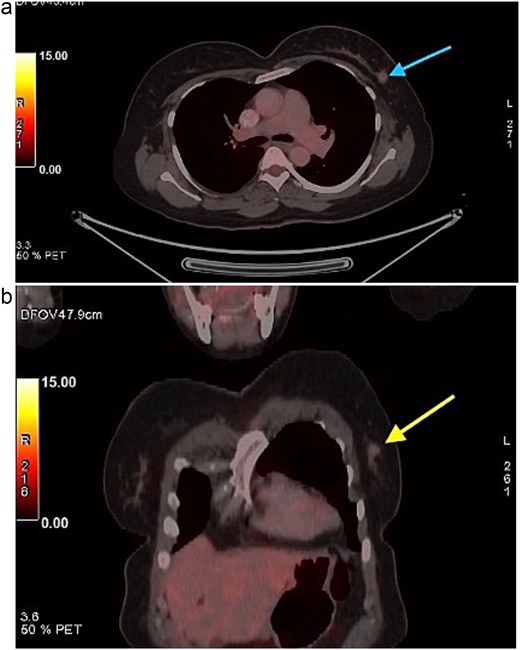

A 58-year-old woman with no relevant family history underwent routine health screening during which a left breast lump was detected. Mammography showed a high density spiculated lesion in the upper outer quadrant (BIRADS 4c/5) (Fig. 1a and b). Ultrasound demonstrated a 1.0 × 1.1 cm spiculated, heterogeneous hypoechoic lesion (BIRADS 4c). FDG positron emission tomography computed tomography (PET CT) revealed mild uptake confined to the breast lesion (SUVmax ~2.5) with no FDG avid axillary nodes or distant disease (Fig. 2a and b). Ultrasound guided FNAC revealed infiltrating ductal carcinoma (Yokohama Category 5) with cohesive clusters and scattered malignant ductal epithelial cells showing nuclear overlapping, moderate pleomorphism, conspicuous nucleoli, and moderate cytoplasm in a hemorrhagic background.

FDG PET CT images of the chest. (a) Axial PET CT image showing a well-defined FDG avid lesion in the upper outer quadrant of the left breast , consistent with the known carcinoma, with no evidence of axillary or mediastinal lymphadenopathy. (b) Coronal PET CT image demonstrating the left breast lesion in the upper outer quadrant without invasion into the chest wall or adjacent structures, consistent with localized disease.

A critical diagnostic challenge lies in the limited FDG uptake sometimes seen in low proliferative apocrine carcinomas. Reliance on PET avidity alone can therefore lead to underestimation of disease burden; histology and conventional breast imaging remain central to accurate staging [5]. Another frequent pitfall is misclassification as invasive ductal carcinoma NST when AR immunostaining is not performed in ER/PR negative cases. This misstep risks overlooking the apocrine phenotype and its therapeutic implications [3]. Cytological evaluation poses further difficulty, as apocrine cells are typically large with abundant eosinophilic granular cytoplasm and prominent nucleoli, while usual ductal carcinoma cells are smaller [6]. Without awareness of these features and correlation with IHC, misclassification is possible.

Surveillance following treatment of IAC should follow standard breast oncology protocols. FDG PET CT is not reliable for recurrence detection in low proliferative apocrine tumors, reinforcing the importance of structured clinical follow up and mammographic surveillance.